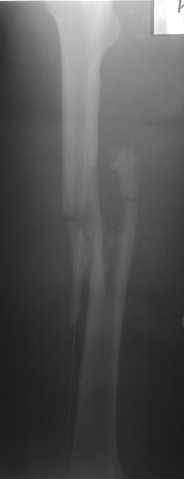

Несмотря на высокоэнергетический характер ранения, пуля не попала непосредственно в кость, а прошла рядом. Таким образом, для бедренной кости это ранение нельзя назватьв полном смысле этого слова высокоэнергетическим. К сожалению, не видно выходное отверстие. В любом случае, при таком переломе интрамедуллярный остеосинтез вполне показан. Кроме того, если пациент попал к Вам в первые часы после ранения, рана не должна рассматриваться как инфицированная. В качестве примера возможности даже более травматичной операции при таком характере перелома привожу следующий случай.

Пациент оперирован на 5-е сутки (переведен из другого лечебного учреждения)после сквозного пулевого ранения плеча и грудной клетки (непроникающее ранение той же пулей). Выполнен минимально инвазивный остеосинтез блокируемой метадиафизарной пластиной, повторная хирургическая обработка ран плеча. Заживление всех ран первичное, сращение наступило в обычные сроки.